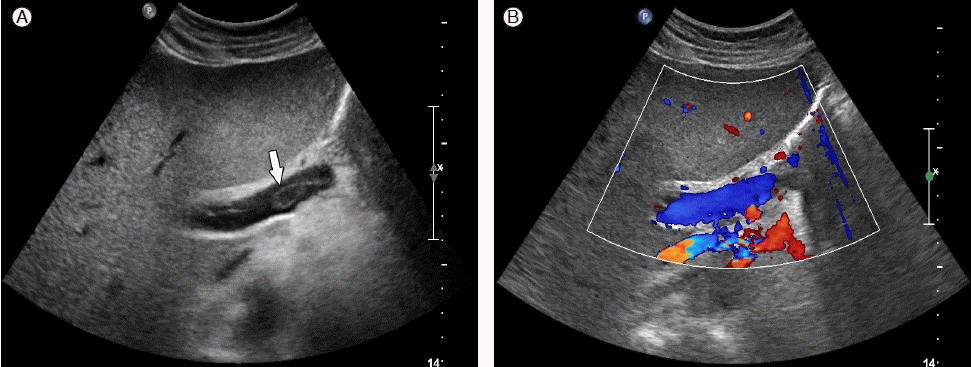

Figure 4.

Follow-up abdominal and Doppler ultrasound. (A) After 8 days, ultrasound of the abdomen shows a partially decreased thrombus (arrow) in the right main portal vein. (B) Doppler ultrasound of the abdomen shows improved portal flow in the right main portal vein.